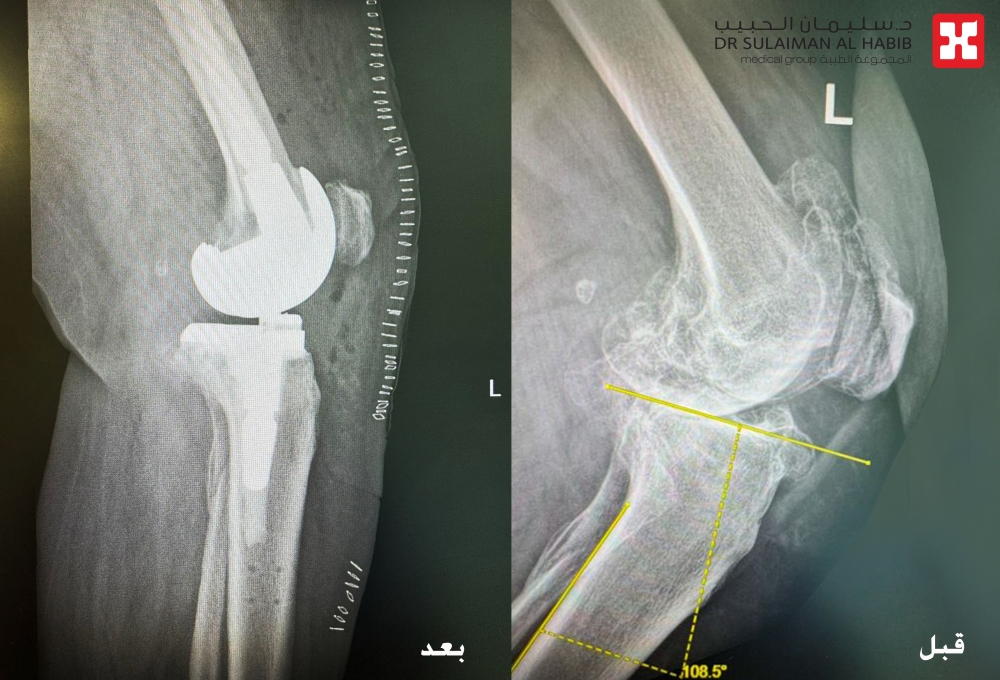

وقال الدكتور سكيك عند وصول المراجعة للعيادة تم الاستماع إلى شكواها والإطلاع على ملفها الطبي، وتبين أنها تعاني من آلام حادة وانتفاخ شديد بالركبة اليسرى منذ سنوات، وعدم القدرة على المشي أو صعود السلم، على الفور تم إخضاعها لفحوصات طبية دقيقة بالأشعة السينية (Digital X-rays) على كافة إتجاهات الركبة، بالإضافة إلى التحاليل المخبرية، مشيراً إلى أن النتائج كشفت عن وجود خشونة شديدة واحتكاك من الدرجة الرابعة، وتآكل بالغضاريف المحيطة بالركبة اليسرى، وكذلك الكشف عن تكلسات خلف الركبة، بالإضافة إلى حدوث انحراف وتقوس بالركبة، وكذلك إصابتها بمجموعة من الأمراض المزمنة مثل ضغط الدم والكوليسترول وهشاشة عالية بالعظام.

موضحاً بأنه بعد الانتهاء من دراسة كافة نتائج الفحوصات، تم اتخاذ القرار بالتدخل الجراحي، مشيراً إلى أن العملية استغرقت ساعتين ونصف تحت التخدير الجزئي، وتم فيها استخدام تقنية الروبوت الجراحي المتطور، والذي تم تزويده بالمعلومات الخاصة بالمراجعة، حيث يقوم الروبوت برفع قياسات مفصل الركبة بشكل دقيق، وتحديد المفصل الصناعي المناسب، مما يمنح الحالة نتائج عالية الدقة، وبما يتناسب مع بنية الركبة والأنسجة المحيطة بها، كما تم تعديل إنحراف وتقوس الركبة من خلال استخدام دعامة متطورة بالساق والفخذ.